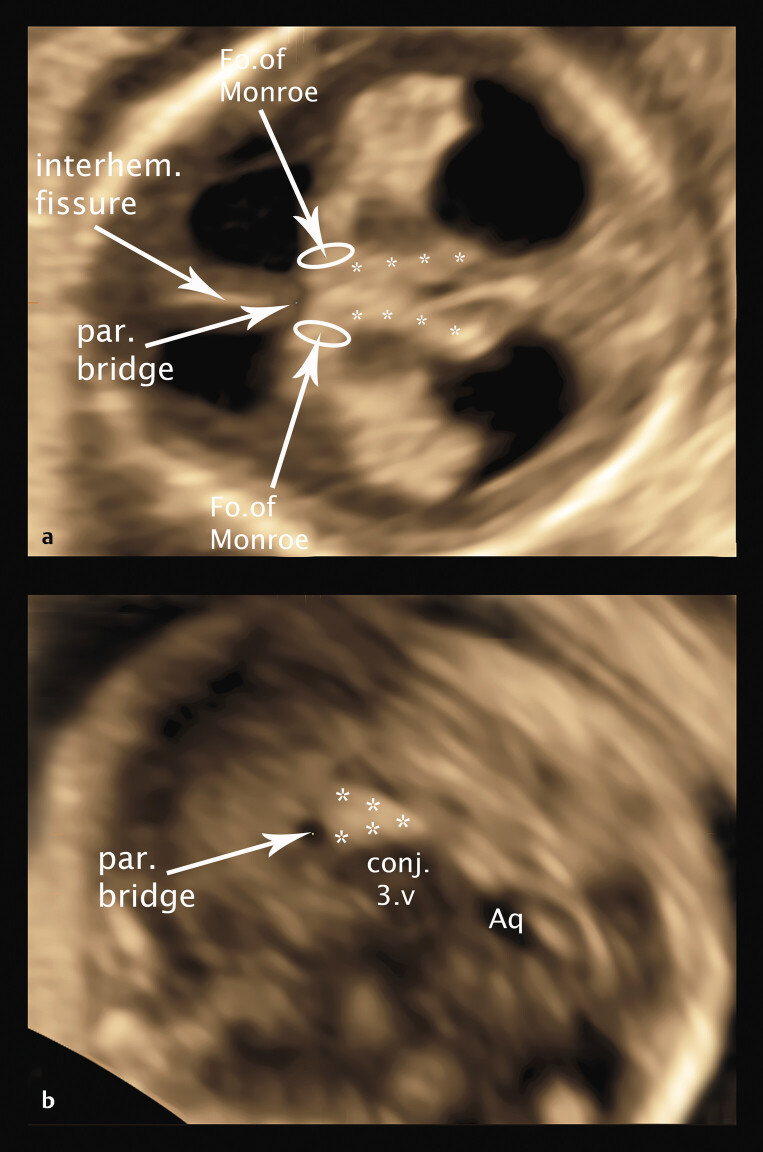

目的探讨高危妊娠冠臀长度为45 ~ 84 mm胎儿的幕上结构——未来透明隔腔、间腔、第三脑室、神经节隆起和丘脑/下丘脑的超声异常。材料和方法本研究回顾性分析了64例胎儿经阴道记录的胎儿脑3D体积,这些胎儿的母亲在GW 12-14期间因胎儿的有机和/或遗传变化向我们的门诊就诊。在这项研究中,我们选择了具有最佳超声质量的胎儿脑3D体积块的胎儿,以便对幕上脑结构进行详细分析和测量,并将结果与遗传分析结果、妊娠后期超声控制和胎儿结局相关联。结果在44例遗传改变胎儿和20例综合征改变胎儿中,27例胎儿发现脑结构改变,并将脑结构与近期发表的妊娠早期12-14周脑结构进行对比分析,首次揭示了早期病理性脑发育的新细节——迁移障碍、轻度前脑畸形(大叶畸形、MIH)、胼胝体发育不全。结论经阴道三维超声可通过直接超声病理分析和病理结果可视化,高质量地检测和分析GW 12-14脑幕上缺损。

Purpose   To detect sonographic abnormalities of the supratentorial structures of the brain - future cavum septum pellucidum, cavum velum interpositum, third ventricle, ganglionic eminence and thalamus/hypothalamus - in fetuses with a crown-rump length of 45-84 mm in high-risk pregnancies. Materials and Methods   This study presents the retrospective analysis of transvaginally recorded 3D volumes of the fetal brain of 64 fetuses whose mothers consulted our ambulatory department for fetomaternal medicine for organic and/or genetic changes of their fetuses at GW 12-14. For this study we selected fetuses with 3D volume blocks of the fetal brain at best sonographic quality enabling detailed analysis and measurement of the supratentorial brain structures to correlate the results with the results of genetic analysis, ultrasound controls in later weeks of pregnancy, and fetal outcome. Results   Of 44 fetuses with genetic changes and 20 fetuses with syndromic changes, structural brain changes were found in 27 fetuses, analyzed by correlating the brain structures with the recently published structures of the brain at gestational week 12-14 in early pregnancy, presenting new details of early pathological brain development - migration disorders, milder variants of holoprosencephaly (lobar, MIH), corpus callosum agenesis, for the first time in early pregnancy. Conclusion   Supratentorial defects of the brain can be detected and analyzed in GW 12-14 in detail by direct analysis of sonopathology and visualization of pathological measurements using transvaginal 3D sonography in high quality.